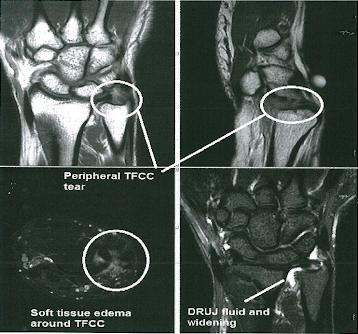

Skafolunat bağ yaralanmaları en sık görülen el bileği yaralanmalarıdır. Bu bağ skafoid ve lunat kemiği bir arada tutar. Bu bağın bozulması skafolunat instabilitesine neden olur. Geç aşamalarda skafoid ve lunat kemik arasında bir boşluk oluşur ve skafolunat ayrışması olarak bilinir.

Skafolunat instabilitesinin semptomları ağrı, sertlik ve şişliği içerir. Bunlar ilk önce splintleme ve steroidal olmayan antiinflamatuar ilaçlarla ve daha sonra kortizon enjeksiyonlarıyla tedavi edilebilir. Bu tedaviler başarısız olursa ameliyat bir seçenek olabilir. Artritik olmayan aşamada bağ rekonstrüksiyonu tercih edilen cerrahidir.